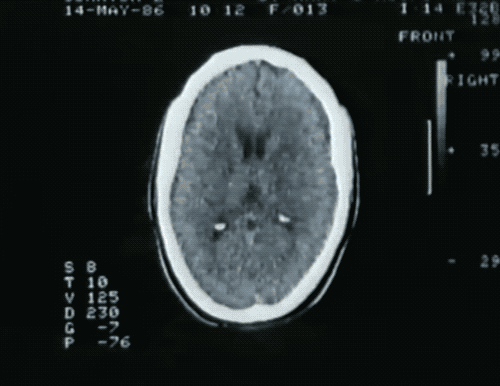

他的颞叶、额叶等许多被认为和高级认知功能有关的脑区都遭受了病毒的攻击。其中,海马体是受伤最严重的部位。大病过后,原本是海马体的地方只剩下一个海马形状的空洞。

病毒在Clive的大脑里凿出了洞,使其失忆。